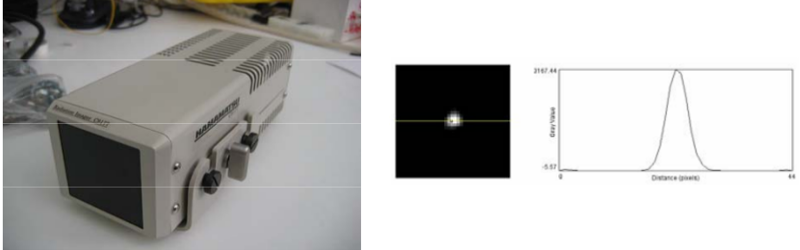

This work reports on the development and evaluation of the PET component of a PET/CT system for small-animal in-vivo imaging. The PET and CT subsystems are assembled in a rotary gantry in such a way that the center of rotation for both imaging modalities is mechanically aligned. The PET scanner configuration is based on 2 detector modules, each of which consist of 2 flat-panel type PS-PMTs (Hamamatsu, H8500) and 2 (30 × 30 elements) LYSO arrays.

In this work we characterized a recently developed gamma imager for small animal SPECT applications. The Hamamatsu C9177 is a mini-gamma camera that integrates the detector and all the electronics, including the acquisition system, in a compact and portable housing. The detector is based on a high resolution parallel hole collimator, a CsI(NaI) crystal array and a PS-PMT (flat panel type). |